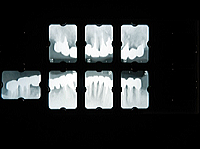

(写真4)初診時のX線写真

虫歯による歯冠の崩壊が著しく、惨憺たる状況になっていました。

残根は結果的に11本抜歯をすることになりました。

(写真12)治療後のX線写真

『現存する歯は17本になりましたが、

この残された歯を大切にこれ以上失わないように、メンテナンスをきちんとやっていきましょう。